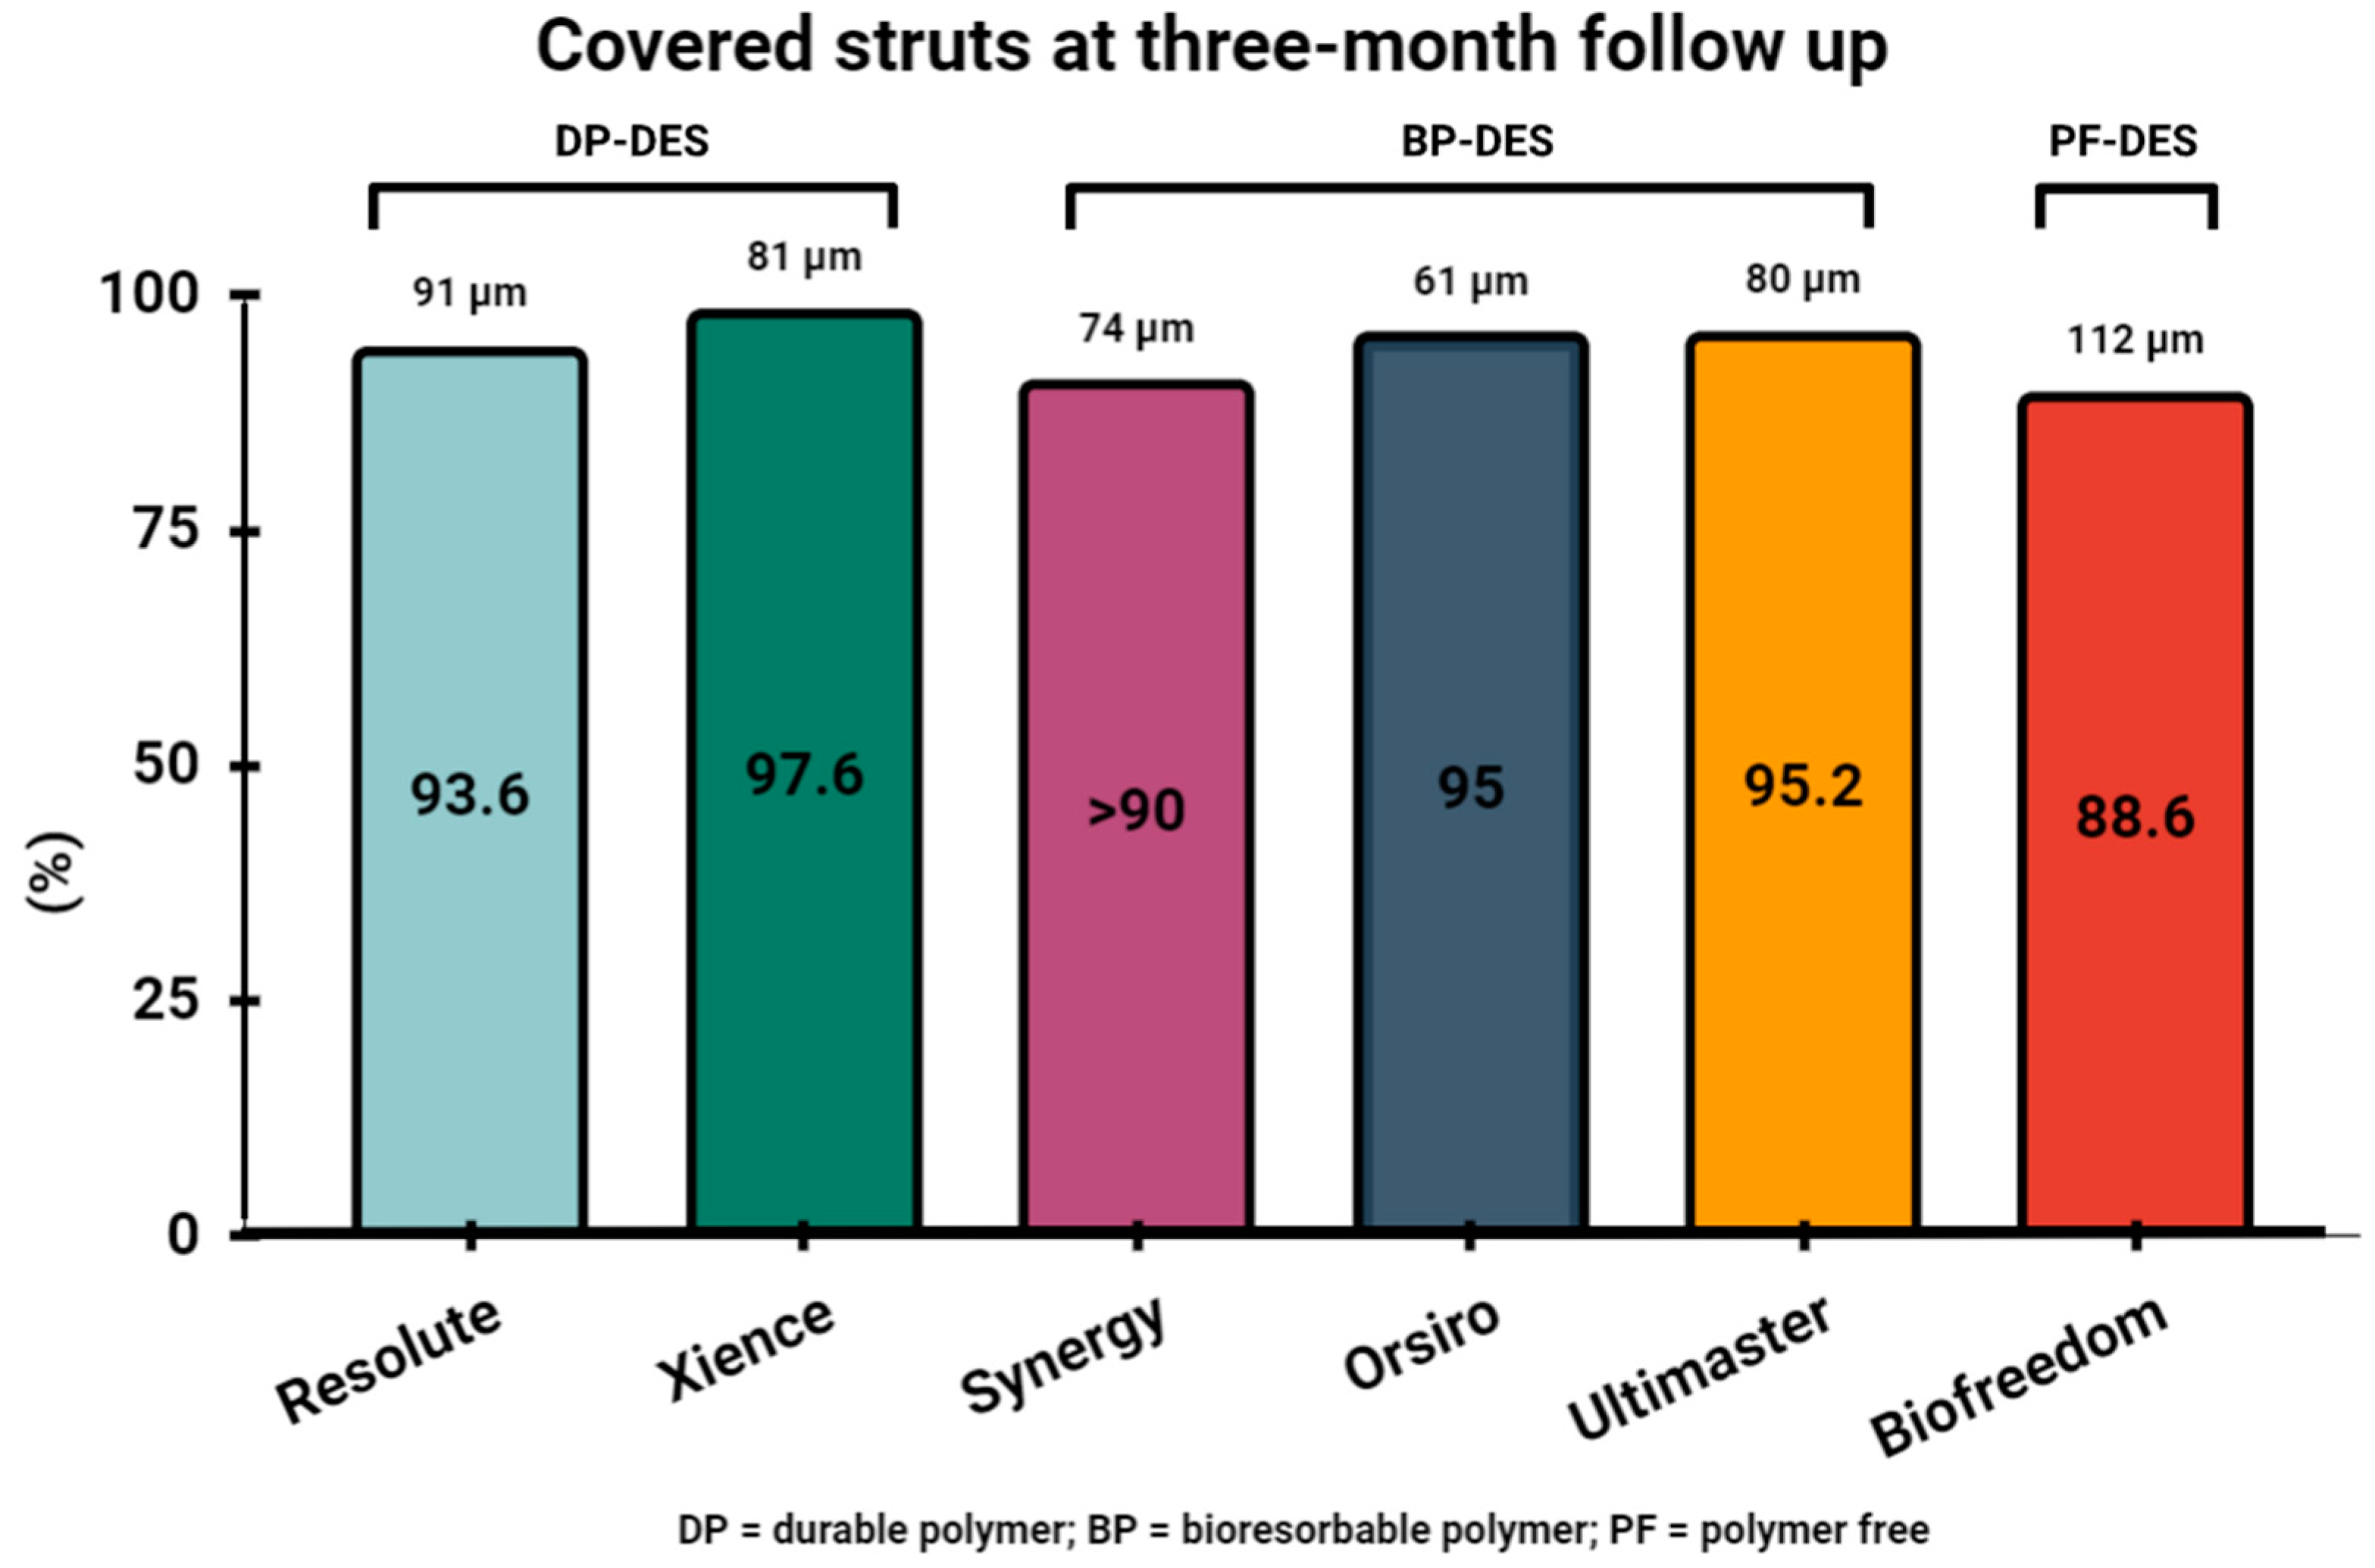

6. Assessment of Stent Healing by OCT Three Months following PCI and Safety of Three-Month DAPT